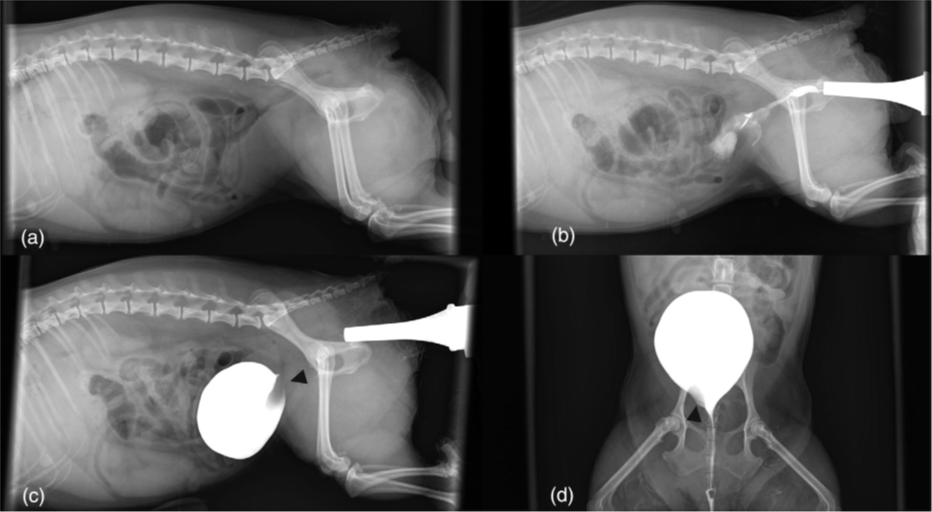

Tras una exhaustiva evaluación llevada a cabo mediante la combinación de Tomografía Computarizada con contraste, cistoscopia, radiografías y ecografía, se detectó que tenía una duplicación de vejiga en el plano coronal y una sola uretra, que además iba acompañada de una infección urinaria.

“La mayoría de los casos existentes acerca de la duplicación completa de la vejiga en el plano coronal también hablan de una duplicidad en la uretra. En este caso, sin embargo, la paciente solo tenía una uretra, conectada a la vejiga principal”, explica el equipo de Medicina Interna, Diagnóstico por Imagen y Cirugía de AniCura Ars que ha llevado a cabo tanto el diagnóstico como la extirpación quirúrgica de la vejiga duplicada.

Si la vejiga accesoria no cuenta con un uréter, retiene orina y no permite el acceso de los antibióticos, por lo que se crea un entorno ideal para el crecimiento bacteriano y la infección urinaria recurrente. “Cuando llegó a nuestro hospital, la paciente llevaba un año con infecciones de orina recurrentes, con recaída al terminar los antibióticos y con episodios intermitentes de disuria, polaquiuria y hematuria. Sin embargo, la exploración física era normal”, comenta el equipo que ha llevado con éxito el caso, formado por Jordi Puig, Luis Feo, Núria Vizcaíno, Elísabet Domínguez y Diana Gomes.